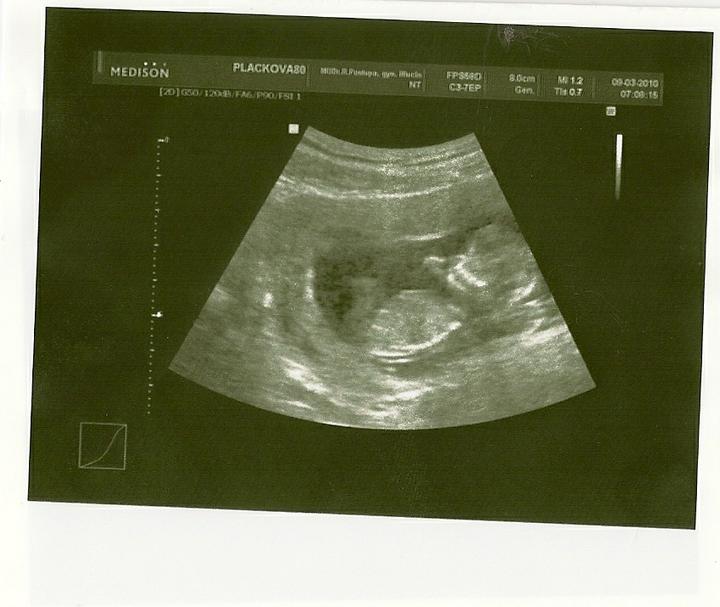

Velký UTZ ve 20 týdnu za námi_vše v pořádku....

asi budeme mít holčičku 🙂